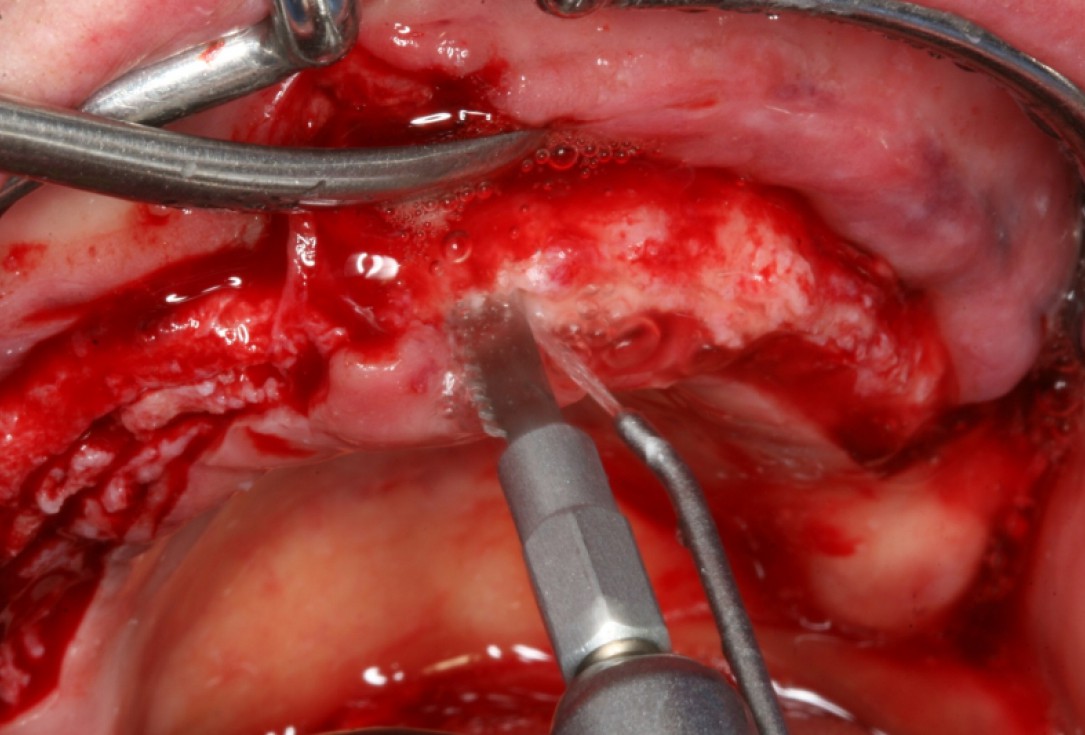

02/10 - Deep bone splitting with oscillating saw in regio 15 to 25Circular bone splitting with maxresorb® & collprotect® membrane - PD Dr. J. Neugebauer